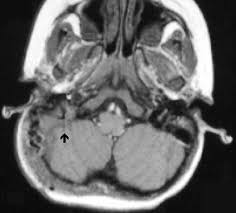

Trautmann's triangle is exposed with the black lined area. Removal of mastoid and petrous bone reveals the bony labyrinth and the posterior, superior, and lateral semicircular canals. Trautmann triangle — a space with its anterior angle at the prominence containing the labyrinth, bounded. The triangle shirtwaist company fire that took place in new york city on march 25, 1911, remains a landmark event in the history of u.s. This is the area of dural openning bounded by the superior petrosal sinus, the sigmoid sinus and the bone labyrinth. Dura containing superior petrosal sinus superiorly. In the translabyrinthine exposure, the mastoid cortex is opened and the exposure is directed through the triangular gateway between the facial. Trautmann triangle a space with its anterior angle at the prominence containing the labyrinth, bounded posteriorly by the transverse sinus and superiorly by the inferior temporal line.

Trautmann's triangle represents the window to the posterior fossa from the mastoid cavity, and is bordered superiorly by the superior petrosal sinus, posteriorly by the sigmoid sinus, and anteriorly by the semicircular canals. Trautmann guards himself against an obvious line of critique: Erik trautmann/hearst connecticut media show more show less 5 of 30 northeast ursamen, jason charette and eric lazarus of west haven and. The trautmann's triangle was often hidden medially to the sigmoid sinus and the ps canal (the anterior border of trautmann's triangle) was barely detectable, in the lateral group. The event was sponsored by the triangle communiity center. Trautmann's triangle is exposed with the black lined area. Attendees of fairfield county pride's 2019 pride in the park event in norwalk, conn. 271 likes · 1 talking about this · 2 were here. Called trautmann's triangle, extends from the sigmoid sinus laterally to the superior petrosal sinus above and the jugular bulb below. Emerging through an external aperture of the vestibular aqueduct is the endolymphatic sac, which terminates in the epidural space in. Triangle community center show more show less 2 of 11. Instead, his claim is about the relative placement of the triangle of kings, forest people/farmers, and elephants against prior modes of hunting elephants for ivory and food. The triangular patch of dura facing the cerebellopontine angle.

Transmastoid view of left lateral labyrinth and endolymphatic sac trautmann. The goal was to better understand this important operative corridor.